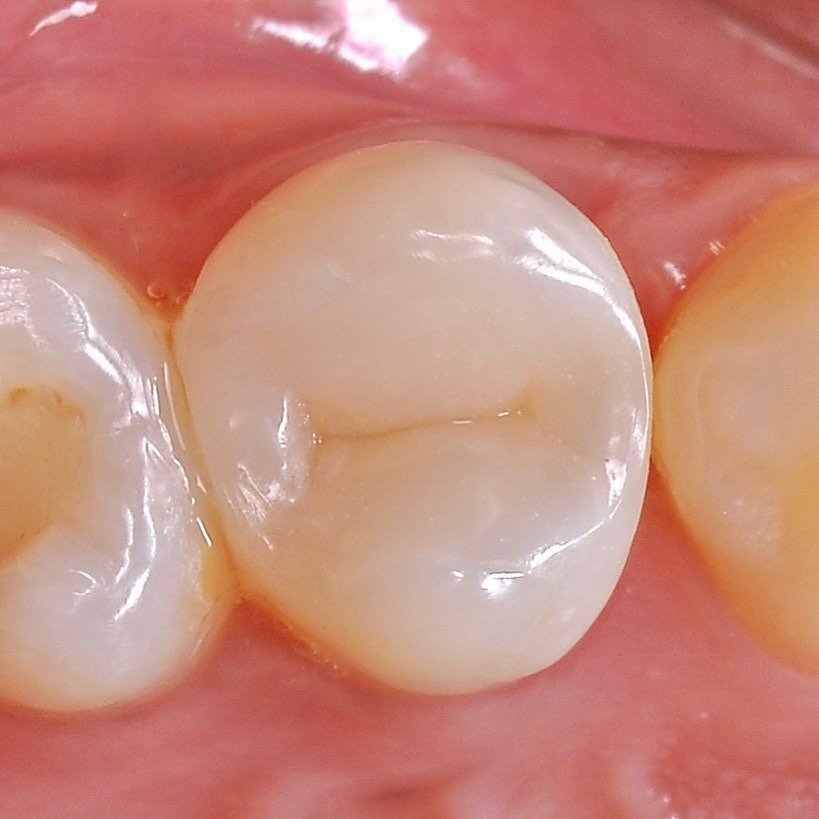

strengthening the tooth with fiberglass

we install a crown on the cured tooth